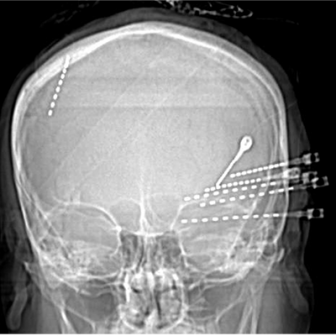

Stereoelectroencephalography (SEEG)

EEG scalp recording cannot always identify the exact location of where a seizure starts. Some people will need further testing, which can be done using intracranial electrodes such as depth electrodes. SEEG surgery is needed to put these special electrodes in place. Your neurologist and neurosurgeon will discuss all options and information about the surgery with you prior to the operation.

Intracranial electrodes are EEG electrodes that are placed inside the skull in order to monitor seizure electrical activity in the brain as precisely as possible.

Depth electrodes are thin, wire-like tubes with metal contacts. These are inserted into the brain.

The Surgery

Depth electrodes are inserted while you are under a general anesthetic, meaning you are asleep during the surgery. It is called surgery because it is done in the operating room. Depth electrodes are individually inserted by the neurosurgeon with the help of a robot through tiny holes in the skull. Depth electrode wires are attached to the head with small metal bolts. There is no need to shave your hair to have this done.

After the surgery, you will go to the post-anesthetic care unit (PACU) for monitoring until you wake up. Before going to the epilepsy unit, you will go for a CT scan and/or MRI to verify the electrode placement. After this, you will be admitted to the Epilepsy Monitoring Unit (EMU).